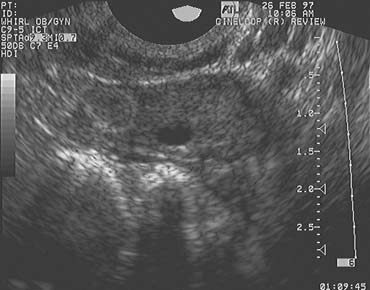

Color Doppler imaging, combined with high-resolution grayscale ultrasonography, provides the means to critically evaluate corpus luteum development and function (Fig. 5). Color Doppler imaging reveals blood flow in the microvasculature that cannot be seen with conventional grayscale imaging and spectral Doppler interrogation generates flow velocity waveforms that may then be analyzed. After corpus luteum regression, the corpus albicans remains visible, at least up until the time of the next ovulation (Fig. 6). Several such structures may occasionally be observed within the ovaries, depending on the proximity of newly emerging small follicles.

Fig. 5. Mature mid cycle corpus luteum with a small central cystic cavity.

Fig. 6. Corpus albicans. The corpus albicans is well-circumscribed by a ring of hyperechoic tissue on the left side of the image of the ovary. This image was recorded on the day before ovulation in the subsequent menstrual cycle.